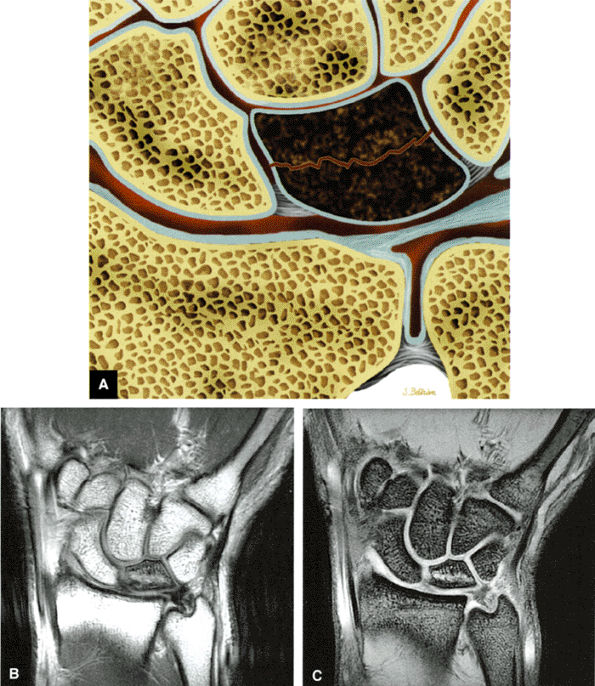

-

Pain and numbness or tingling in the median nerve distribution with increased nocturnal pain and/or burning (can be classified as mild, moderate, or severe based on electrodiagnostic data or by severity of clinical symptoms)

Involvement of the thumb, index, middle fingers, and radial half of the ring finger is most common.

Sensory findings ranging from minimal hypesthesia to complete anesthesia

Muscle atrophy and loss of function are usually late findings, although abductor pollicis brevis involvement and opponens weakness may be seen earlier (opponens atrophy is a late finding).

Positive clinical tests for nerve entrapment: